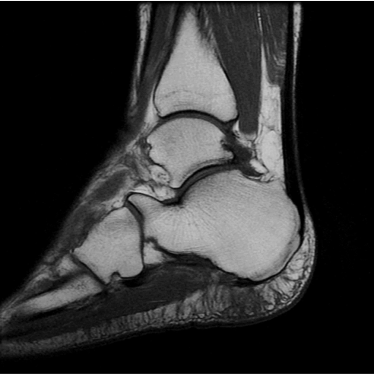

1:29 min촬영속도의 혁신, IAI

기존

IAI

IAI는 AI Deep learning을 통해 기존 장비의 촬영 프로토콜을 최적화합니다.

기존 프로토콜 대비 촬영 시간을 50% 단축시키며, 이미지 퀄리티는 증가합니다.